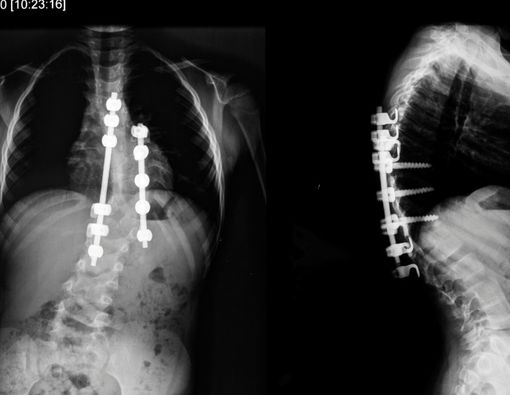

Skoliosis ditandai ketika tulang belakang melengkung ke arah samping. Beberapa orang dengan skoliosis memiliki lengkungan tulang belakang yang tidak normal.

Selain membuat postur tubuh tidak tegak, skoliosis juga dapat menyebabkan rasa sakit, kelelahan, dan bahkan kesulitan bernapas.